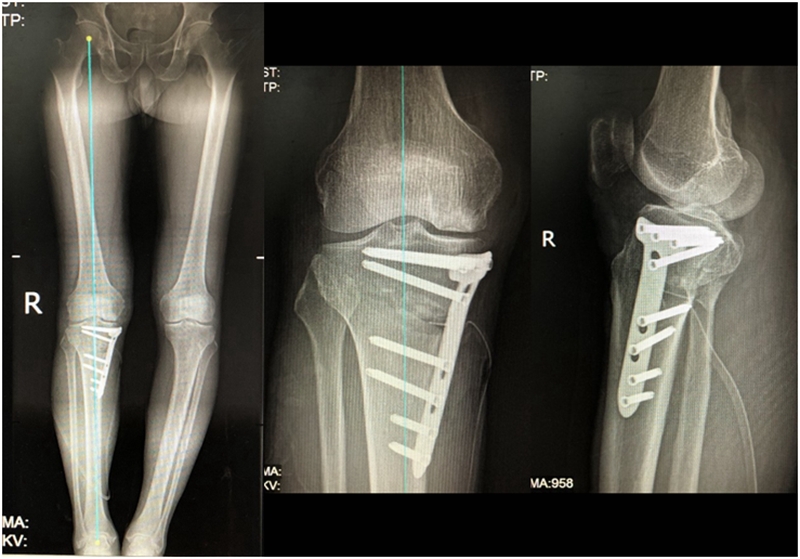

病例3:男,70岁,主诉右膝关节疼痛1年余。查体右膝无肿胀畸形,膝活动度0-120°,内侧间隙压痛。

已经累及44%的股骨内侧髁病变,半月板轻度突出,内侧后角水平撕裂

MRI上深度>20mm

治疗选择保守还是手术?

保守治疗4个月后复查

保守治疗后效果欠佳,坏死范围扩大、塌陷

翻修手术选择截骨矫形还是单髁置换?

最终选择截骨矫形

术后1年1个月

术后2年1个月拆钉

内侧半月板突出未见明显进展